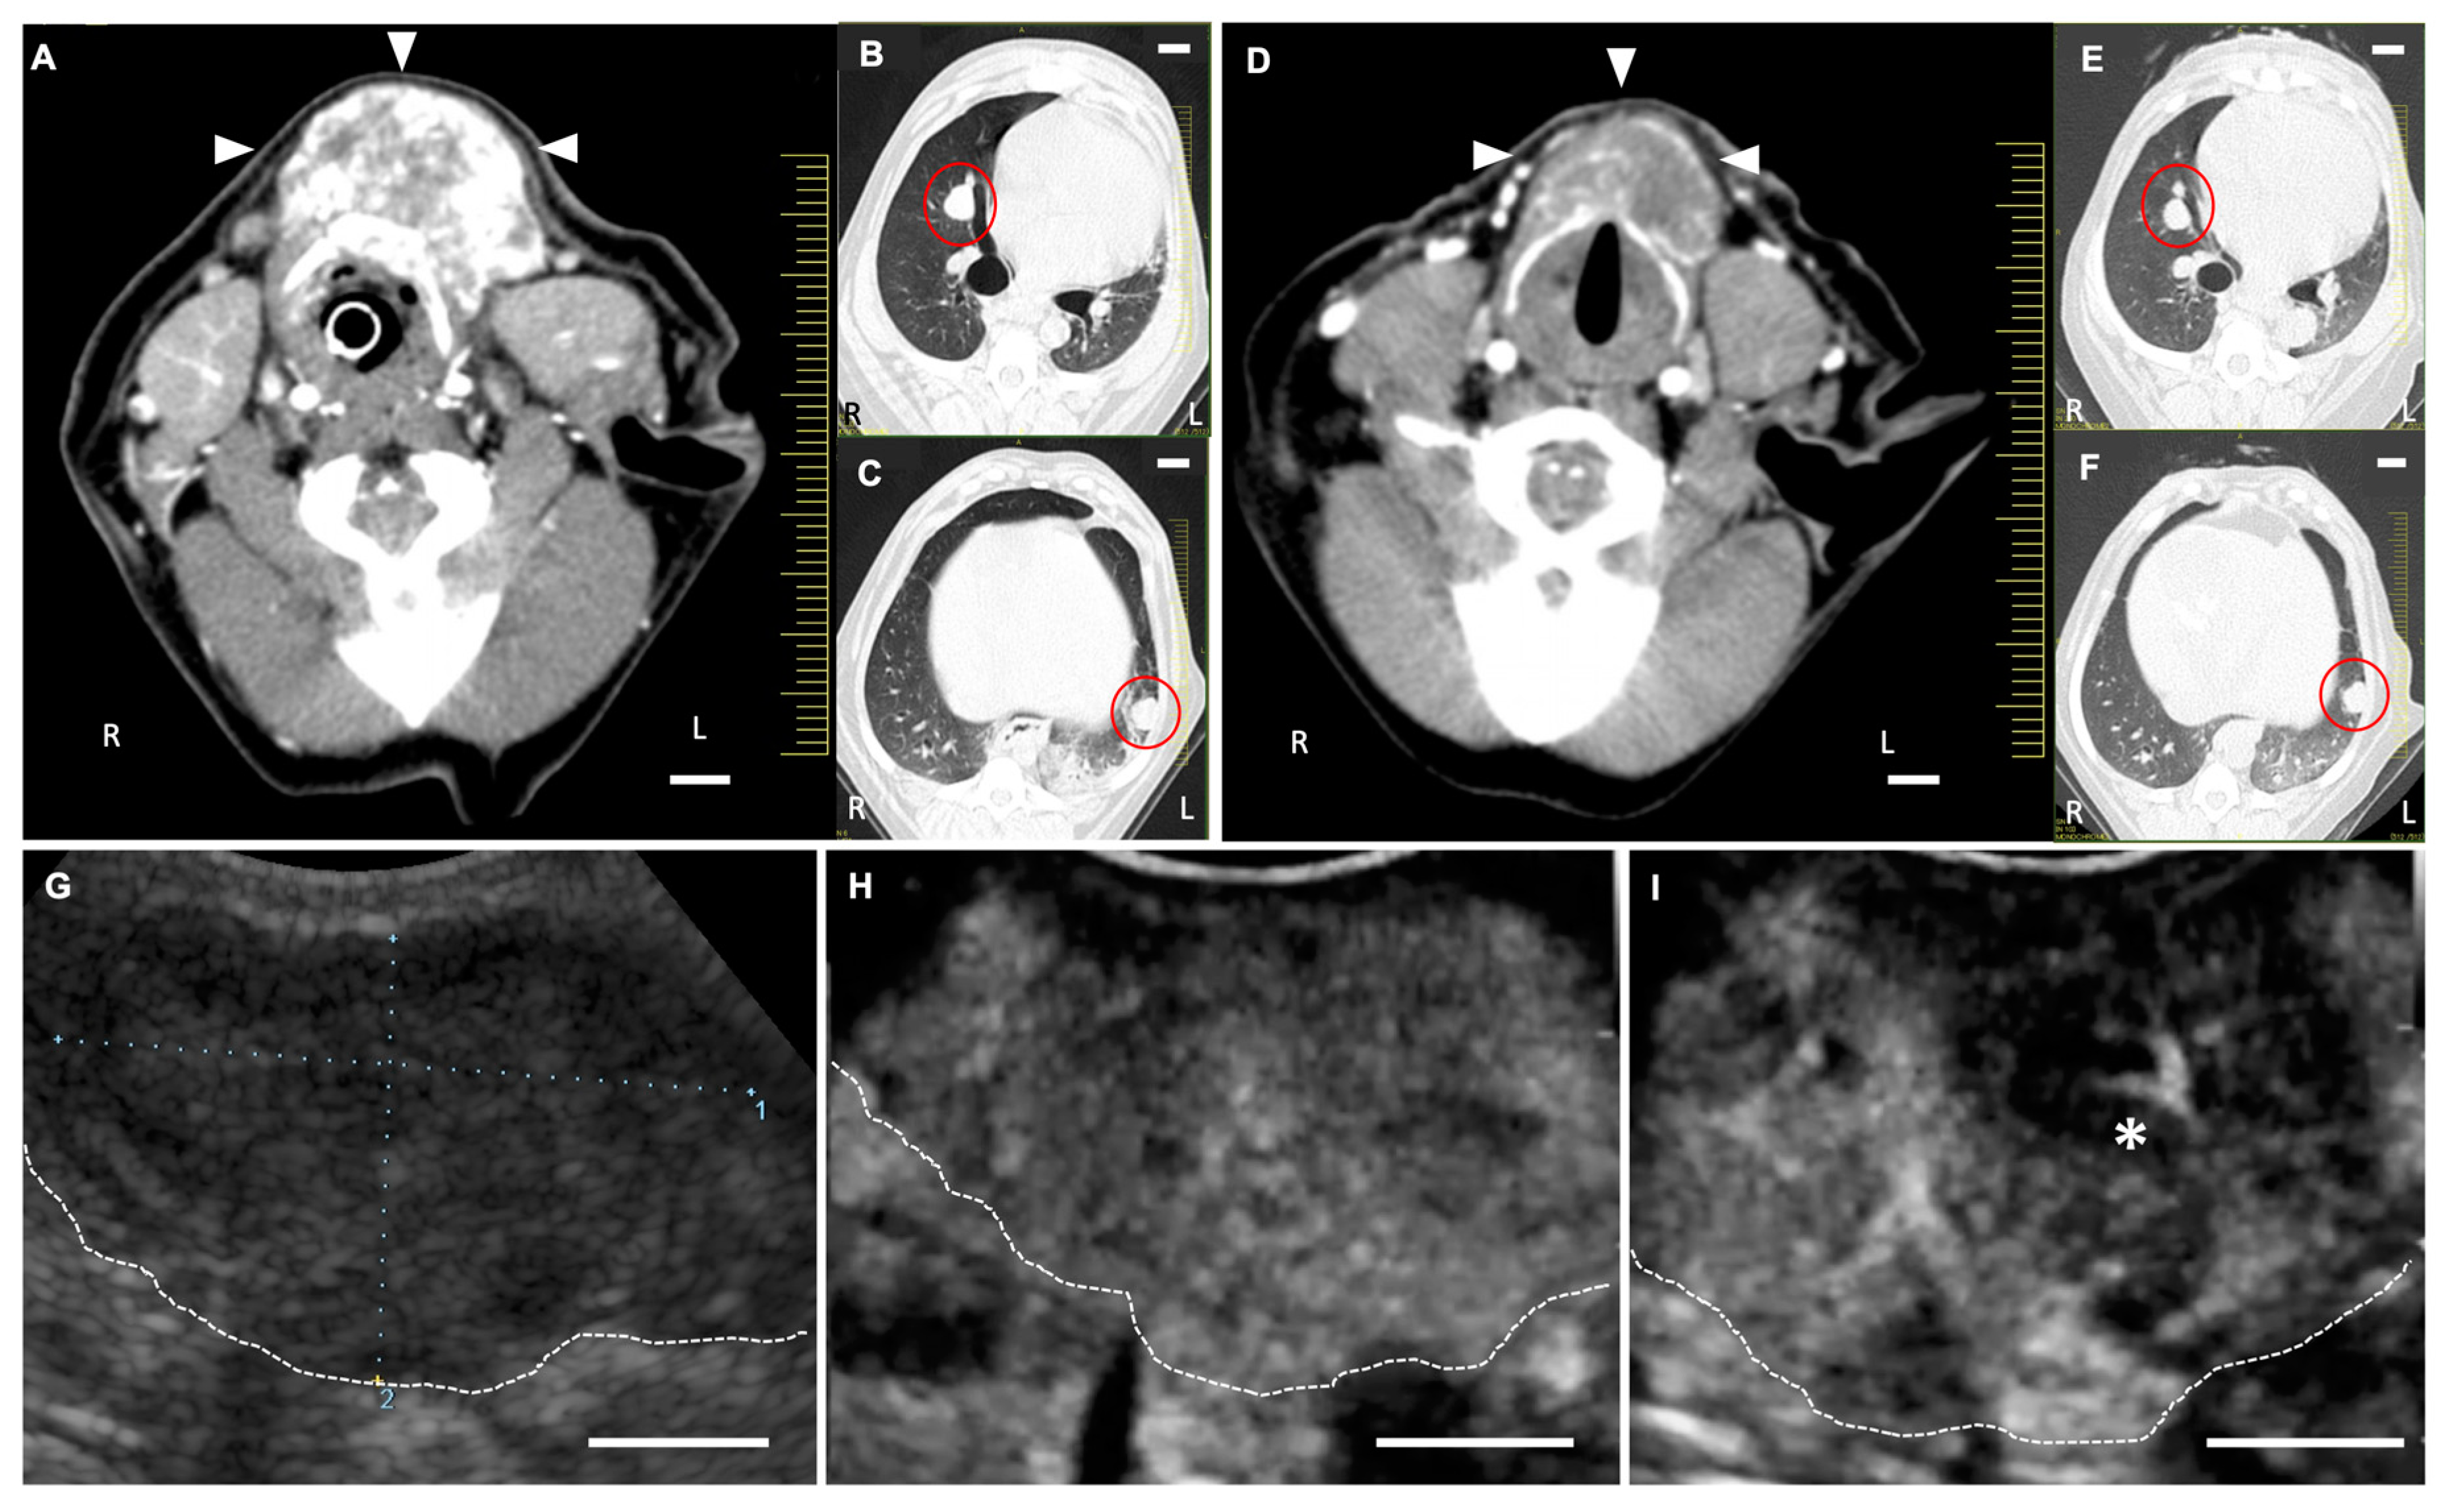

2.3. Anti-Tumor Effects of LBs in Combination with Therapeutic US and Liposomal Doxorubicin

4.4.1. Animals

4.4.2. Treatment Protocol

4.4.3. CEUS for the Assessment of Tumor Vasculature

4.4.4. Measurement of Tumor Size